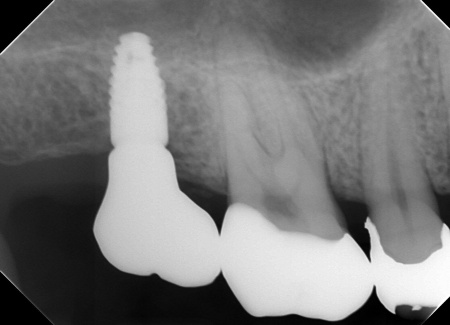

・インプラント治療

保存が難しい左下奥歯(第2大臼歯)と、すでに欠損していた右上の部位については、インプラント治療を行います。インプラント治療とは、顎の骨に人工歯根を埋め込み、そこに人工歯を取り付ける治療方法です。

まず、保存が難しい左下奥歯(第2大臼歯)を抜きます。抜歯後は骨が治癒するまで経過観察を行い、治癒したことを確認後、インプラントの埋入手術を行いました。

右上の欠損部位についても、同じくインプラント治療を実施しています。